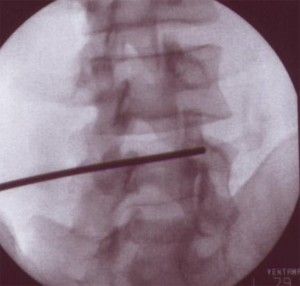

TÉCNICA

El paciente se coloca en  decúbito prono con una almohada en la zona abdominal para disminuir la lordosis lumbar si fuera necesario, se recomienda una visión radiológica antes de decidir si es conveniente o no su empleo. La técnica se realiza con sedación consciente. Se localizan los niveles patológicos con una proyección en AP. Una vez identificados los niveles se elimina el doble contorno de los cuerpos vertebrales con una inclinación del Rx en el plano axial (cráneo-caudal). El arco se va rotando en dirección oblicua ipsilateral a la lesión hasta que aparece en la pantalla la imagen del “scotty dog” . Con esta imagen se introduce la aguja en visión túnel hasta hacer contacto óseo con la unión entre la apofisis articular superior y la apofisis transversa, por encima del ojo del perrito. El punto diana es la parte posterior de la apófisis transversa debajo de la parte medial de su borde superior o la parte media entre el borde superior de la apófisis transversa y el ligamento mamilar. Por último se comprueba la localización de la punta de la aguja con una imagen en  lateral, la aguja debe estar colocada en la línea facetaria, posterior al agujero foraminal y por debajo del disco intervertebral. En algunas ocasiones se puede comprobar la localización de la aguja con una proyección AP, en este caso la punta de la aguja estará localizada en la unión del proceso articular superior y la parte más medial de la apófisis transversa.

Cuando se realiza el tratamiento sobre el ramo medial de L5 hay que tener en cuenta algunas diferencias. El ramo medial a este nivel transcurre en un valle formado por la apófisis articular superior del sacro y el ala del mismo. Para conseguir ver este punto es necesario realizar una rotación en el plano axial del Rx para distanciar la creta ilíaca. Cuando se consigue esta imagen la aguja se dirige en visión túnel a la parte más alta del valle, que está formada por el ala del sacro y su apófisis articular superior.